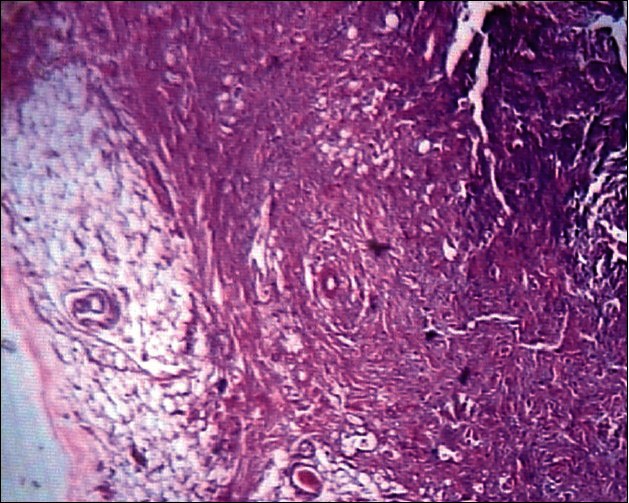

We present a case report of a 45-year-old lady with history of swelling on right side of the nose since two years. On clinical examination, there was a firm swelling, 3 × 2 cm in size, just above the right nasoalar crease, nontender and mobile. Computed tomography revealed fibrous tissue over anterior surface of the right maxilla and nasal bone with mild sclerosis of the right nasal bone. Excision was done through lateral rhinotomy incision. Histopathological examination of the excised specimen revealed spindle cell lipoma which is very rare. Very few cases have been reported in the literature so far.